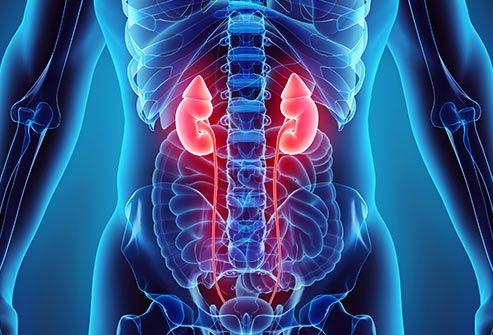

4.9 Thận

Còn được gọi là huyết khối tĩnh mạch thận, những cục máu đông này thường phát triển chậm và chủ yếu ở người lớn. Bạn có thể sẽ không có các triệu chứng trừ khi một mảnh vỡ ra và nằm lại trong phổi của bạn. Hiếm khi, đặc biệt là ở trẻ em, nó có thể xảy ra nhanh chóng và gây buồn nôn, sốt và nôn mửa. Bạn cũng có thể bị tiểu ra máu và đi tiểu ít hơn.